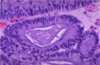

Normal Small Intestine

Normal Colon